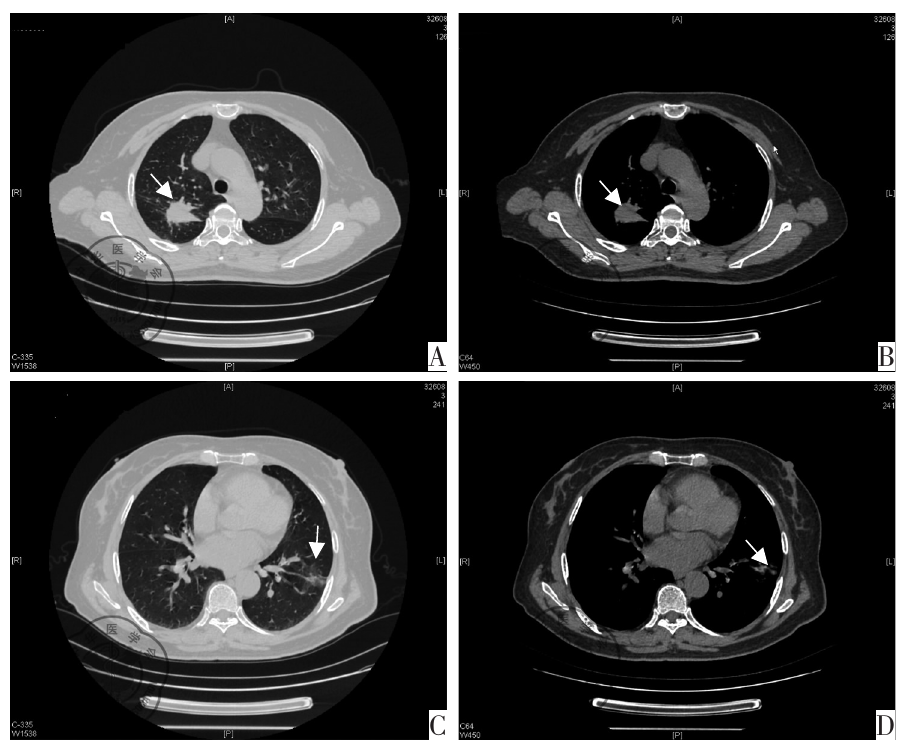

图1 患者治疗前。图A为肺窗显示右肺上叶后段实性片状、结节影,边缘欠规整,周围少量模糊影(箭头);图B为纵隔窗显示增强后中度不均匀强化,其内见无强化低密度影(箭头);图C为肺窗显示左肺下叶外侧基底段实性结节影(箭头);图D为纵隔窗(箭头)